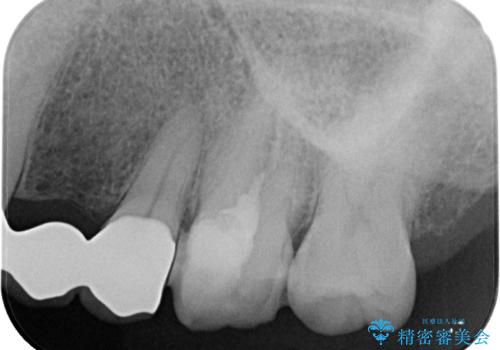

やはりむし歯は大きく、一部歯髄を切除することとなりましたが、その後は良好な経過をたどっています。